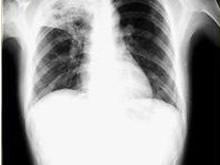

1958年以来我国各地相继证实,腺病毒除引起上呼吸道感染外,还可引致小儿肺炎,多见于6个月至2岁的婴幼儿腺病毒肺炎最为危重,尤以北方各省多见,病情严重者也较南方为多。华北、东北及西北于1958年冬及1963年冬有较大规模的腺病毒肺炎流行,病情极其严重。